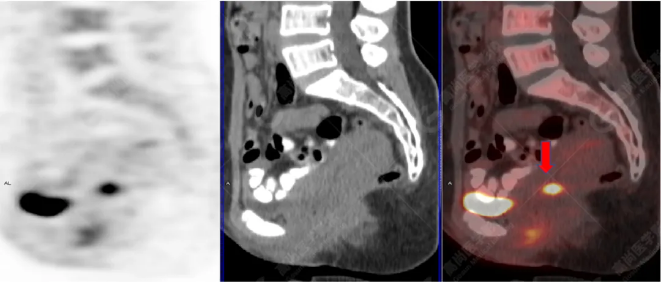

PET/CT影像圖

左胸一后肋溶骨性骨質(zhì)破壞,周?chē)檐浗M織形成,F(xiàn)DG代謝增高,SUVmax為10.9。

找到引起骨痛病灶,病因:原發(fā)?轉(zhuǎn)移?感染?

宮頸一片狀稍低密度影,F(xiàn)DG結(jié)節(jié)樣代謝增高,SUVmax為10.2。

最終診斷:宮頸癌伴肋骨單發(fā)骨轉(zhuǎn)移。